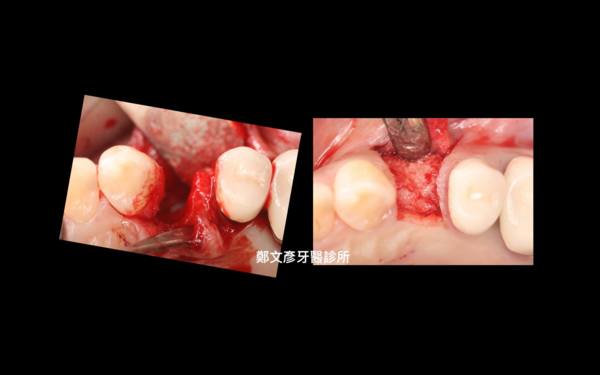

Role of granulation tissue in socket preservation

3. Role of granulation tissue in socket preservation